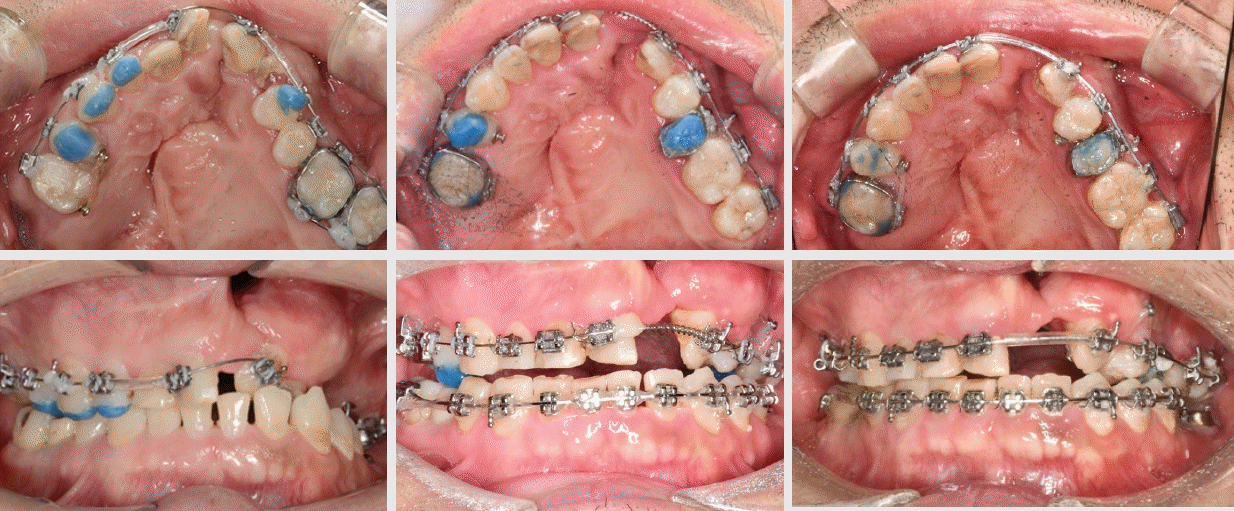

Figure 3.

Unilateral cleft lip and palate male adult patient, axial view of no previous bone graft/ orthodontic treatment history, maxillary archform compared to a diagram9.

치과교정치료 이력이 없는 36세 성인 남성이 치과교정과로 의뢰되었다. 환자는 언어장애 2급 판정을 받았으며, 하악 좌측 대구치의 동통을 주소로 장애인 치료 센터를 내원하였다(Figure 2). 의과병력으로는 유아기에 구순열 및 구개열 관련 수술에 대한 가족의 진술이 있었다. 치료가 가능하지 않은 상악 좌측 제2 대구치와 하악 좌측 제1 및 제2 대구치 발치가 이루어졌고, 치주질환 및 치아 우식에 대한 치료가 진행되었다. 이어서, 하악 좌측 임플란트 식립과 2개월 뒤 이차 수술이 진행되었다. 이 시점에서, 상부 보철물 수복 공간이 부족하며 교합 및 치아위치 개선이 필요하다는 의견에 따라 치과교정과로 의뢰되었다.치과교정과로 의뢰되어 온 환자에게서 구순열 수술 이력을 확인할 수 있었고, CBCT 상의 Axial image에서는 상악 좌측 측절치의 결손과 치조열을 뚜렷하게 확인할 수 있었다. 상악궁 구강 내에서는 상악 우측 제2대구치의 발거, 상악 우측 제2소구치 결손, 상악 좌측 측절치의 결손 및 상악 좌측 유견치(또는 과잉치)의 잔존 치근이 관찰되었으며, 견치 후방에서 위치하였고 치아우식증에 이환 되어 있었다. 구강위생 관리에 대한 교육 및 보존적인 처치와 관리가 요구되었다. Lesser segment 인 좌측 소구치와 대구치의 악궁은 협설 방향으로 위축되어 전반적으로 람다 (λ) 형태의 상악궁 형태를 보였다.따라서, 구강악안면외과의 협진을 의뢰하여, 해당 잔존치근의 발거하였고, 치조골 이식술을 계획하였다. 구강외과 회신서는 "성장기 치조열 수술 시기를 놓치고... 매우 큰 편측성 구순구개열로...., palatoplasty, alveolar bone graftdhk cleft palate 수술 동반 예정 "이라고 하였다. 그리고, 골이식을 위하여 일차적인 치아의 배열을 요청하였다.Figure 4에서 관찰되듯이, 상악 우측 제2소구치와 좌측 측절치 결손을 동반한 치조열의 잔존과 구개열 수술의 결과로 인하여, 람다 (λ) 형태의 상악궁 형태는 상악과 하악의 횡적인 부조화를 야기시켰다. 이는 CBCT의 Coronal section상에서 확인되었듯이, 제1 대구치 위치의 양측성 구치부 반대교합으로 이어졌으며, 하악 좌측 구치부 임플란트의 크라운을 형성할 공간이 결여와 대합이 가능하지 않은 상황을 보여주고 있다. 구순구개열 환자의 포괄적인 진단과 치료 계획에 의한 치료의 아쉬움이 있지만, 하악 임플란트들이 최적의 위치에 식립 되었다는 전제 하에, 상악 제1 대구치 부위의 상악궁을 확장하여 횡적인 부조화를 개선할 것을 계획하였다.따라서, 전방의 골이식을 위한 확장 및 상악 제1 대구치 간의 폭경을 확장시키고자 Quadhelix를 장착하였고, 잠재적인 누공(fistula)의 확장을 최소화하기 위하여 천천히 조심스럽게 확장을 진행하였다. 상악 좌측 제2대구치는 오히려 폭경을 줄이기 위하여 Quadhelix 의 고리를 이용하여 악궁의 중심선 방향으로 견인하였다. 악궁 확장이 진행 과정에서, 필요한 경우에는 반대교합의 해소를 위하여 소구치 교합면 부위에 bite turbo를 적용하였다. 다행스럽게도 구개부의 누공(fistula)들이 확장되거나, 환자가 식사 시 불편감이 있다고 호소하지는 않았다. 상악 좌측 소구치에는 상악 제1대구치의 근심 회전을 막고자 부분적으로 최소한의 배열을 시도하였다(Figure 5).다음 단계로 전치부의 배열, 특히 상악 좌측 견치의 경사를 개선하고자 고정식 교정장치를 부착하고 microimplant를 활용하였다(Figure 6). Microimplant 고정원은 좌측 견치의 치축 개선, 소구치의 협측 이동, 구치부의 구개측 함입에 매우 유용하였다. 악궁의 형태는 삼각형에서 출발하여 점차 형태가 개선되었다 (Figure 6).상악 좌측 견치의 치축 개선을 위하여 greater segment에 대항하여 사용한 코일 스프링의 사용으로 인하여, 중절치의 우측 이동이 발생하였고, 하악 정중선과 일치하지 않은 상태이다. 더구나, 양측 상악 중절치는 6.5mm, 우측 측절치는 6.0mm의 폭경으로 일반적인 전치 폭경에 비해 왜소하다. 상악 좌측의 제2 대구치와 제2 소구치의 선천적 결손을 고려하면, 우측의 측절치 결손 부위는 임플란트 보철을 고려하는 것이 더 좋은 심미적 치료 대안이다. 중절치의 폭경이 평균보다 작고 보철과와 협진 하에 전치부 심미 보철과 임플란트 식립을 위한 재배열을 시행할 계획이다.악궁확장 및 악궁 배열 이후, 좌측 치조열과 전방 구개에 장골이식(iliac bone graft)을 시행하였고, 현재 양호하며, bone consolidation을 기다리고 있으며, 술후 6개월 이후 에 cleft 부위 골이식 공간에 임플란트 식립이 가능하다는 구강외과의 회신을 받았다(Figure 7).